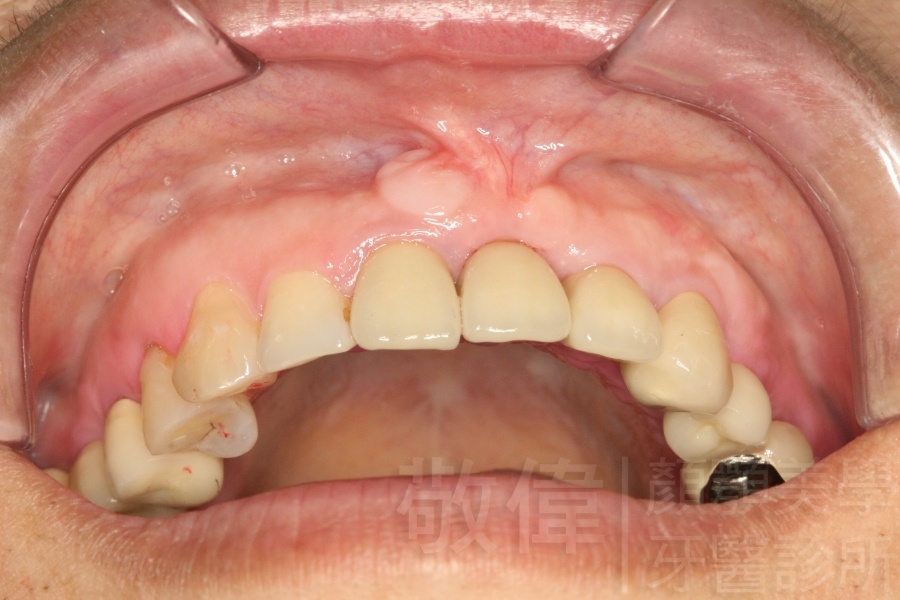

治療前-缺上排前牙   治療後